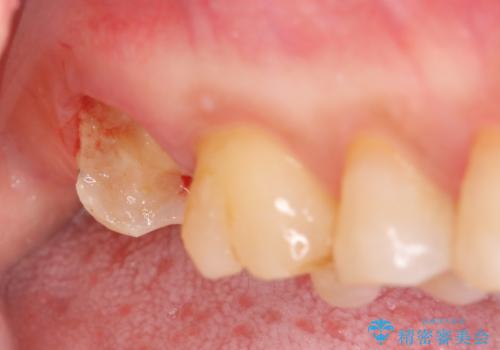

歯髄方向 歯肉方向へと深い 2種類の大きな虫歯

#17は失活歯で歯肉方向への縁下カリエス、#16は生活歯であるものの歯髄ギリギリの処置となるであろうとが予想される治療です。

歯周外科、マイクロスコープを用いた虫歯治療を行い歯を残す治療計画を立てます。